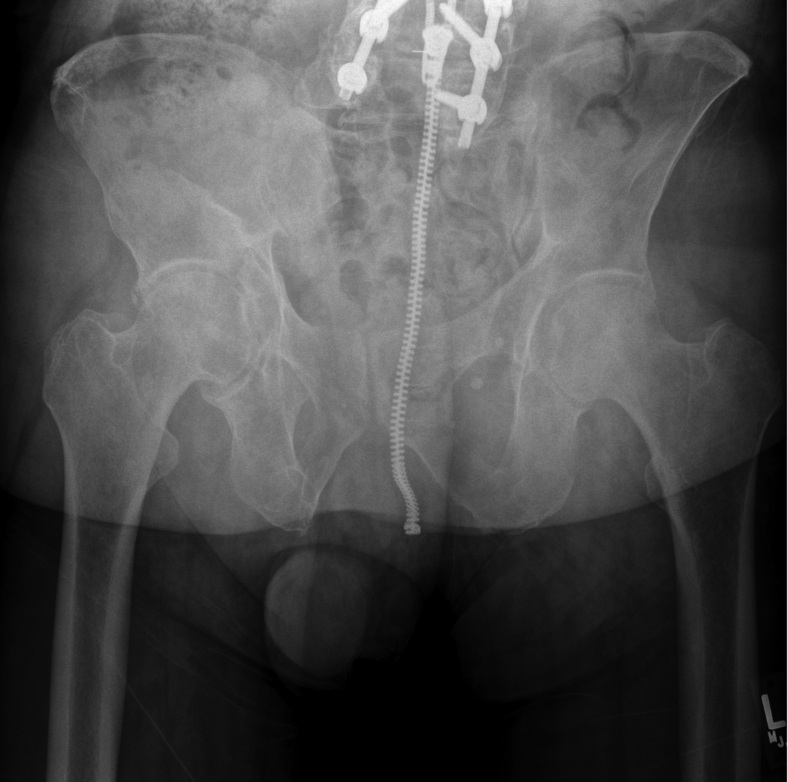

In 2012, a 59-year-old male underwent right THA for end-stage osteoarthritis (Fig. 1). Given the patient’s younger age, the treating surgeon elected to use a cementless THA with a CoC articulation. Using a modified Hardinge approach, the patient received a Lineage 58-mm porous-coated, titanium acetabular component (Wright Medical Group, Memphis, TN) with a 32-mm inner diameter ceramic liner. A Perfecta RS, proximally coated fluted, titanium femoral component (Wright Medical Group, Memphis, TN) was then used, and a +3.5 ceramic head neck assembly was attached. His postoperative course was uneventful without concerns for component complication, malposition, or infection.

Figure 1.

Anteroposterior (AP) pelvis at original presentation showing end-stage right-hip osteoarthritis.